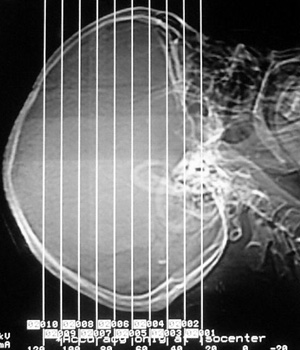

患者,女,49岁,头痛数年,有癫痫病史,无外伤史。

甲状旁腺低下:颅脑 ct 可见以基底节为中心的双侧对称性、多发性、多形性脑钙化的特点。除苍白球外,可广泛分布于壳核、尾状核、小脑齿状核、丘核、内囊及脑皮质、白质等处。